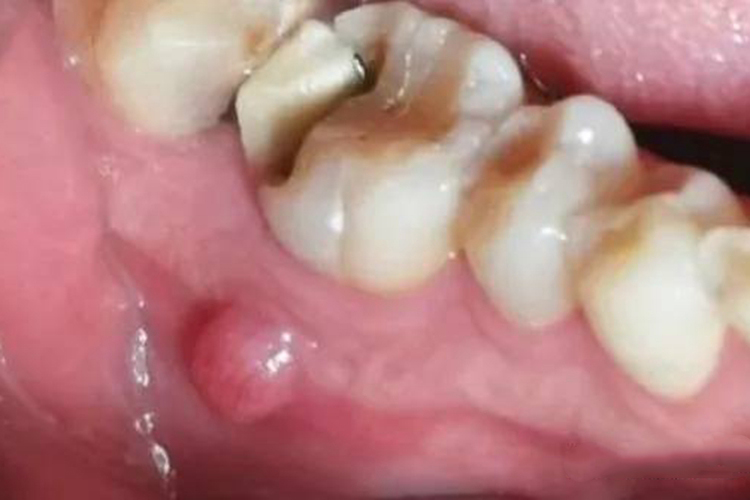

根尖肉芽肿:本病主要为炎性症状,呈圆形异常增生,边界清晰,看起来像一个圆形囊肿,周围骨质正常或稍显致密,直径一般不超过1cm。